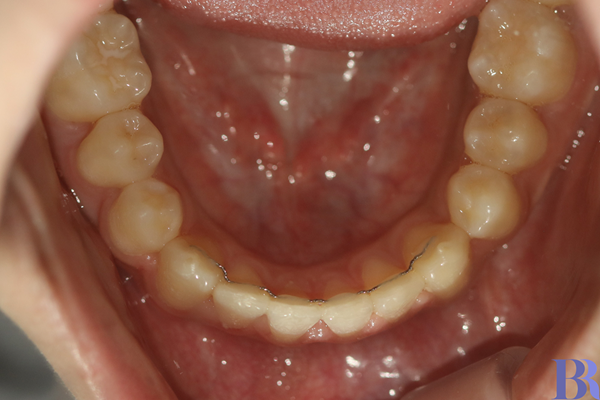

교정전 아래 치아 모습

교정 전 아래 치아 모습입니다.

반대교합이 심하다 보니

아래 치아 앞니가 안쪽으로

심하게 쓰러져 있습니다.

교정 후 아래 치아 모습

교정 후 아래 치아 모습입니다.

쓰러진 앞니가 세워져서

훨씬 더 건강해보입니다.